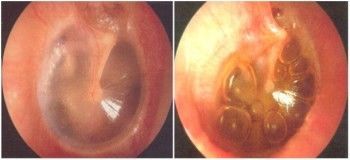

Describe the ear!

Bulging Tympanic Membrane

Acute Otitis Media

Distorted cone of light

Left ear

Treat with penicillin, amoxycillin, co-amoxiclav

Caused by: Streptococcus pneumoniae, haemophilus influenzae, moraxella catarhalis, GAS or S. aureus